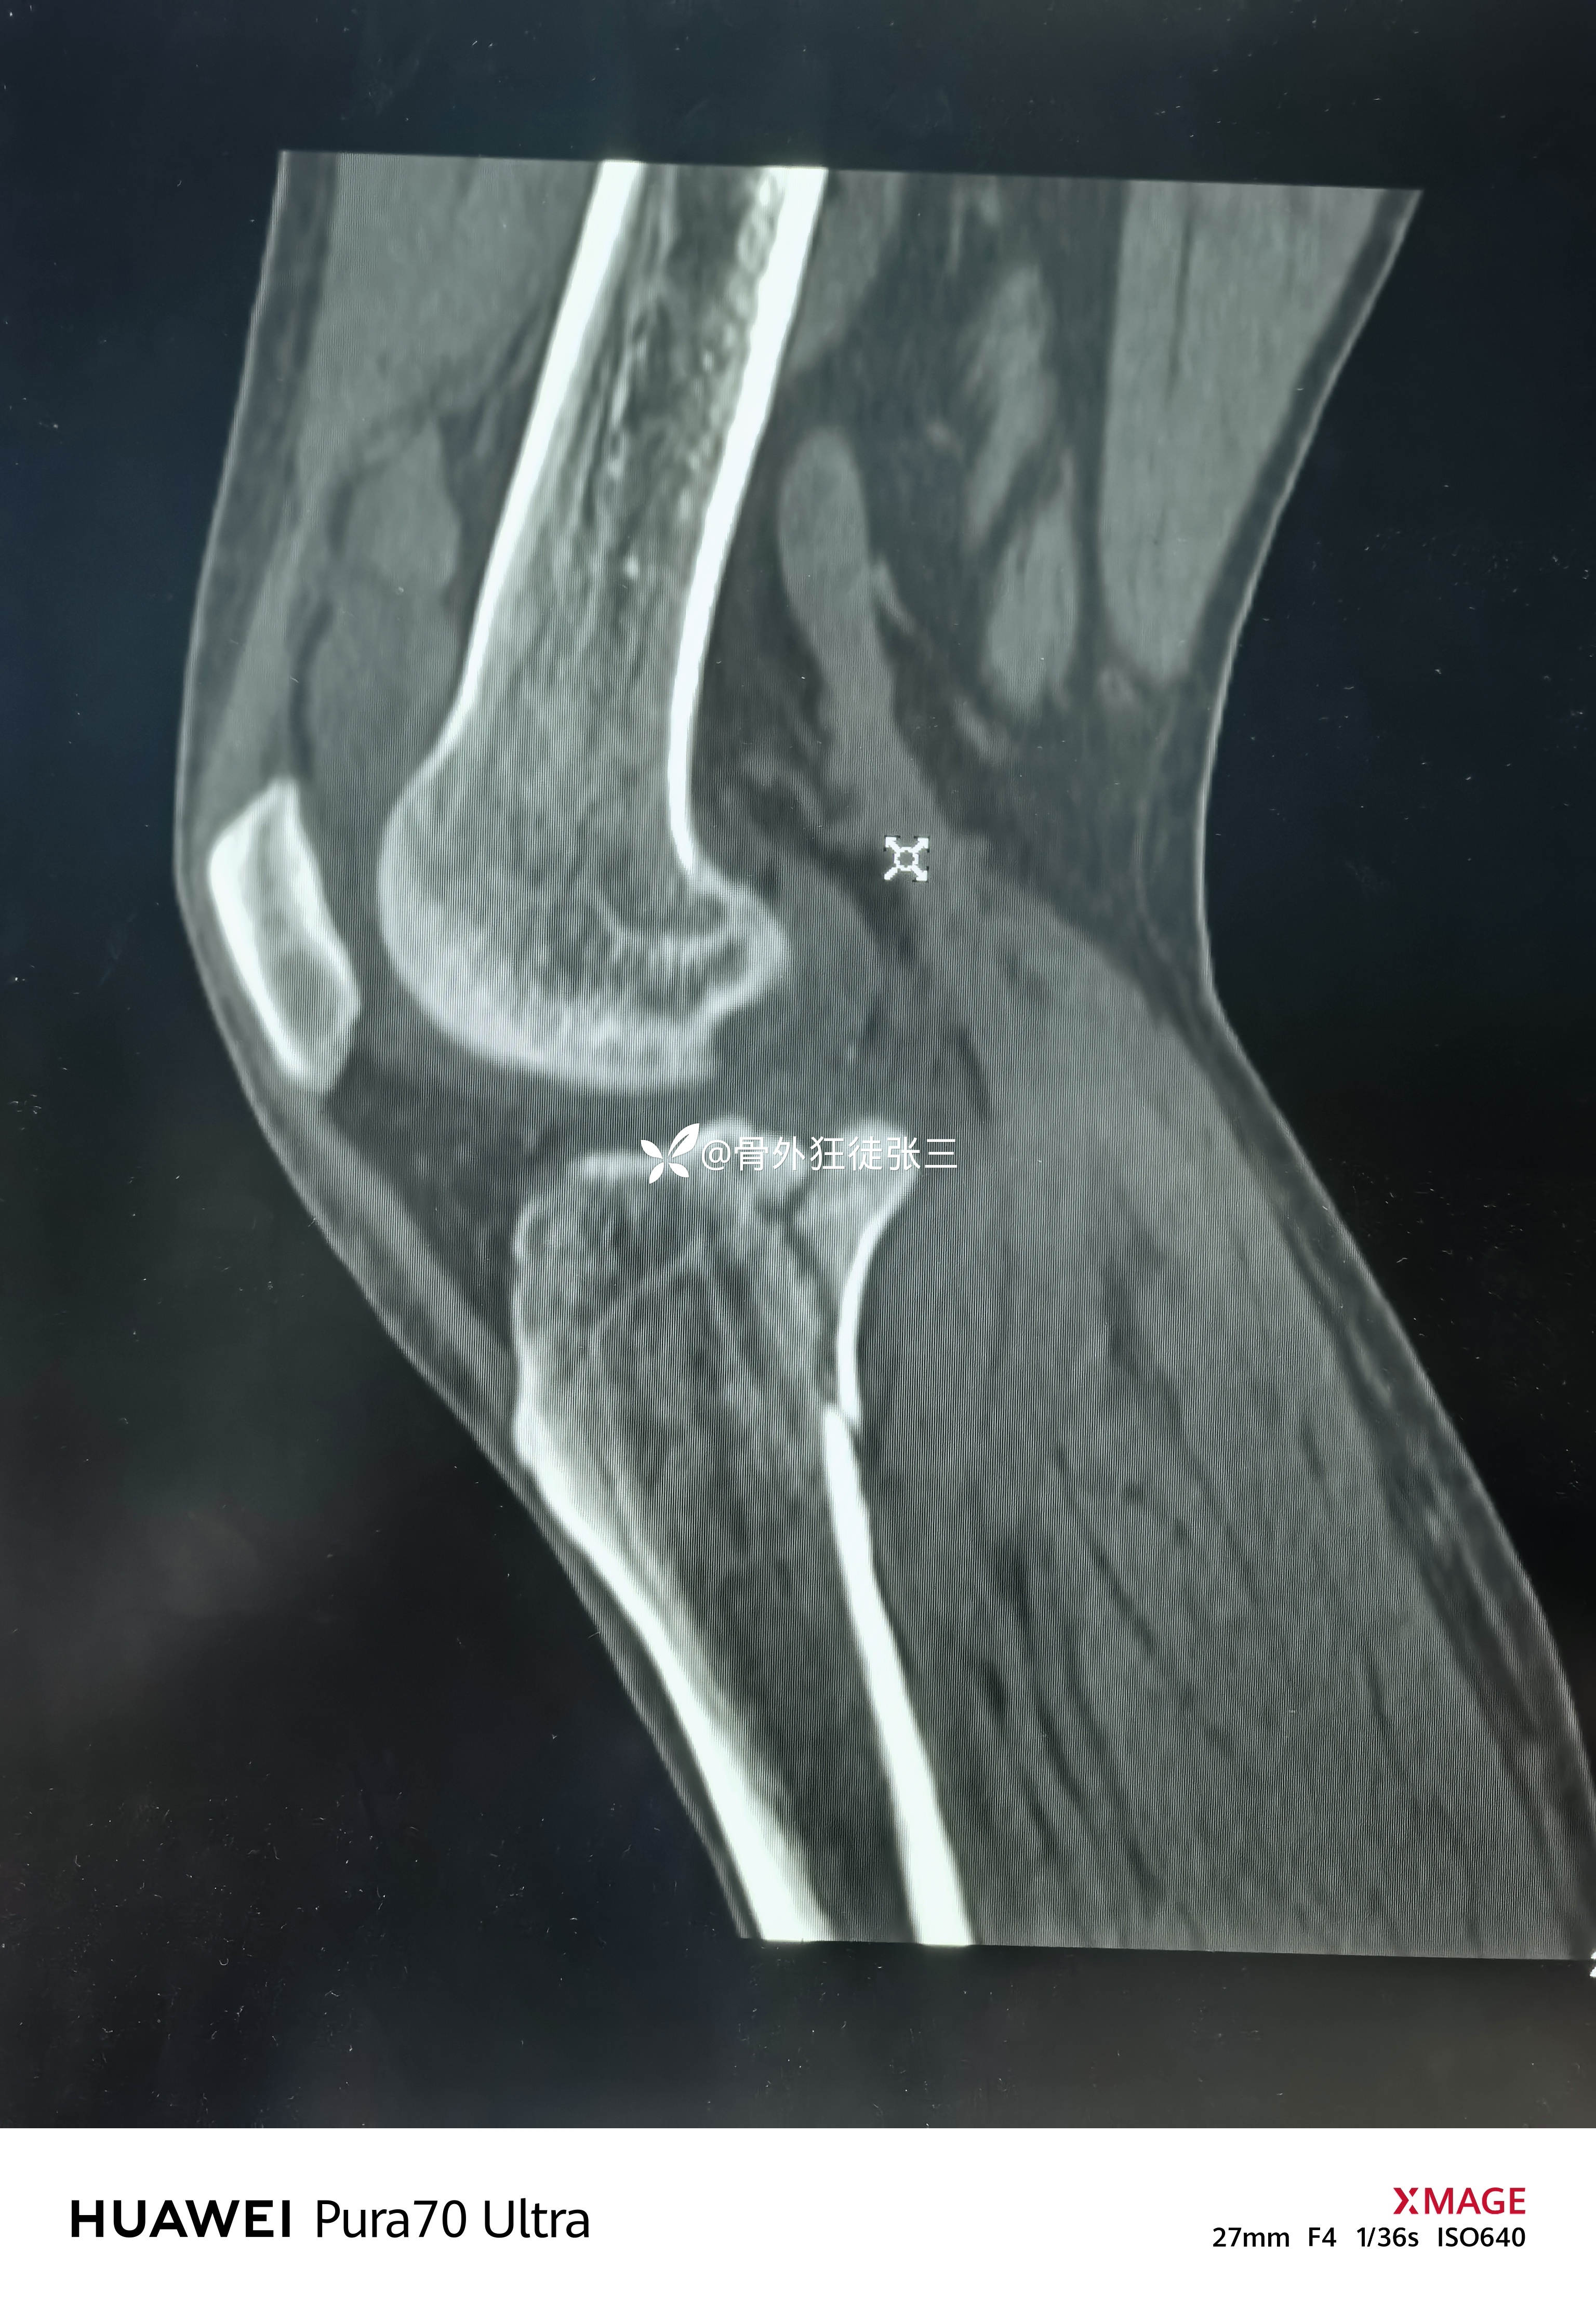

但是CT下显形惊涛骇浪

右胫骨平台骨折

(屈曲内翻型——后内侧平台骨折+外侧平台塌陷+ACL止点撕脱)